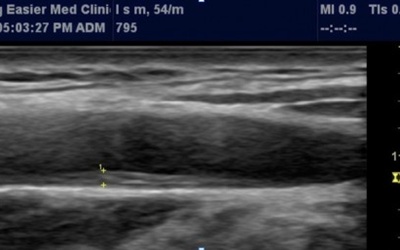

경동맥 초음파 검사는 목 부위에 위치한 경동맥의 상태를 실시간으로 확인할 수 있는 비침습적인 검사 방법입니다. 초음파를 이용하여 혈관 벽의 두께, 혈액의 흐름, 혈관 내 플라크(혈전)의 존재 여부 등을 파악할 수 있습니다. 마치 도로 위에 설치된 CCTV처럼, 혈관 속 상황을 안전하게 들여다보는 것이죠. 검사 과정은 간단하며, 통증이나 불편함이 거의 없어 누구나 부담 없이 받을 수 있습니다.

제가 병원에서 경동맥 초음파 검사를 받았을 때, 검사 시간이 15분 정도로 매우 짧았던 기억이 납니다. 편안하게 누워서 초음파 젤을 바르고, 의료진이 탐촉자로 목 부위를 부드럽게 스캔하는 동안, 저는 마치 휴식을 취하는 듯한 기분을 느꼈습니다. 검사 결과에 대한 설명을 들으면서, 미리 혈관 건강을 체크하고 관리할 수 있다는 점에 안도감을 느꼈습니다.